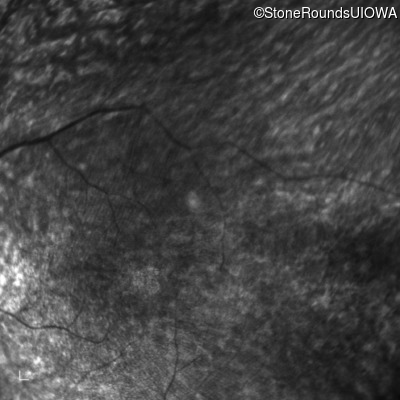

Infrared Fundus Photograph - Left - 10/160 sc

Exemplar